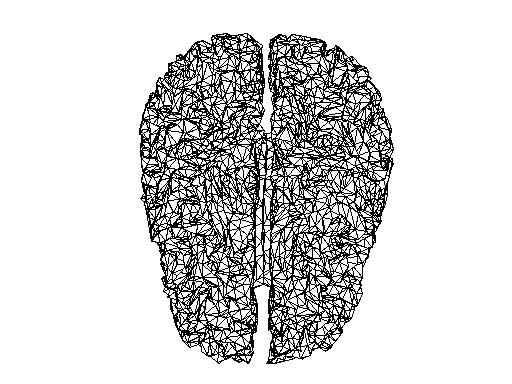

Comparing source spaces

I have read in the source space created on the sample data (subject 10 in Lin’s experiment) into MATLAB.

In MNE:

mne_setup_source_space --ico -6

In MATLAB:

src = mne_read_source_spaces('/<path>/sub10-oct-6-src.fif');

bnd_mne = [];

bnd_mne.pnt=[src(1).rr; src(2).rr];

bnd_mne.tri=[src(1).use_tris; src(2).use_tris + size(src(1).rr,1)];

figure;

ft_plot_mesh(bnd_mne)

And the source space of the same volume created in FieldTrip, and reduced to the same number of vertices with the MATLAB reducepatch function

bnd2_ft = bnd_ft;

[bnd2_ft.tri, bnd2_ft.pnt]=reducepatch(bnd_ft.tri, bnd_ft.pnt, 16384);

ft_plot_mesh(bnd2_ft);